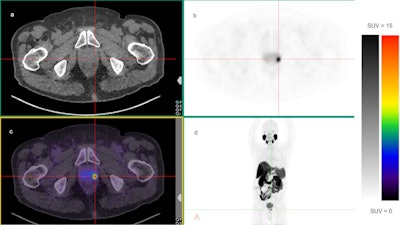

The analysis showed the SUVmax (the maximum uptake of the tracer) of primary prostate tumors was higher in patients with ISUP grades 4 and 5 cancer, compared with ISUP grades 2 and 3 (median SUVmax 19.6 vs. 14.9). Similarly, primary tumor SUVmax was higher in the patient group with PSA > 20 ng/mL than the group with PSA levels between 10 ng/mL and 20 ng/mL.

The researchers found a statistically significant association between ISUP grade (p = 0.004) and PSA level (p < 0.001) with the SUVmax of the primary prostatic tumor observed on F-18 PSMA-1007 PET/CT scans. A higher primary tumor SUVmax was also detected in the high-risk group compared with the intermediate-risk group (median SUVmax 20.2 vs. 11.9; p < 0.001).